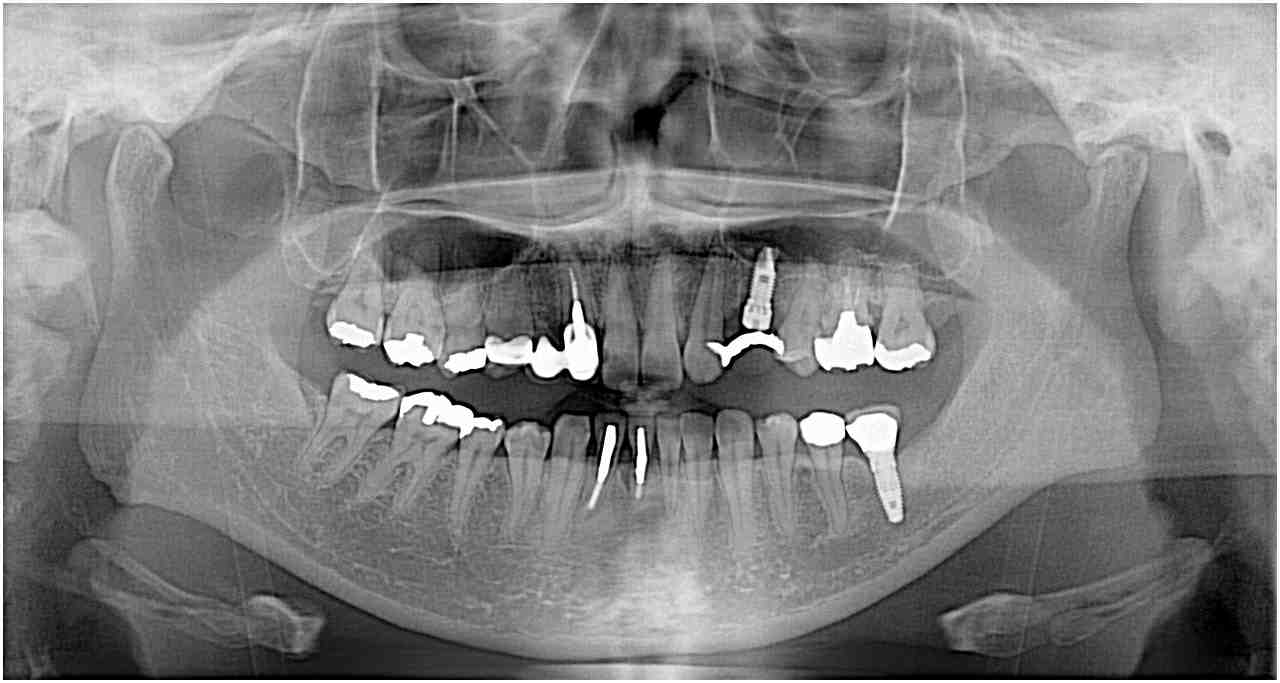

CTデータを基にインプラント設計、計画、埋入までこれを基に行っていきます。| |広島市安佐南区の歯科医院 CTデータを基にインプラント設計、計画、埋入までこれを基に行っていきます。 トップ お知らせ・ブログ CTデータを基にインプラント設計、計画、埋入までこれを基に行っていきます。 CTデータを基にインプラント設計、計画、埋入までこれを基に行っていきます。 Web診療予約 初めての方へ 選ばれ続ける理由 院内設備について 歯が痛いしみる一般歯科 歯がぐらぐらする歯周病 健康な歯を保ちたい予防歯科 子供の虫歯予防をしたい小児歯科 銀歯をセラミックに審美歯科 白い歯を目指しませんか?ホワイトニング 矯正専門医がいるので安心矯正歯科 抜けた歯を補いたいインプラント・入れ歯 医院案内 スタッフ紹介 メリィハウス歯科クリニックオフィシャルホームページ ラベンダー歯科クリニックオフィシャルホームページ お知らせ・ブログ ホーム 診療科目 一般歯科 歯周病治療 予防治療 小児歯科 審美治療 ホワイトニング 矯正歯科 入れ歯・インプラント マウスピース矯正 初めての方へ 院長・スタッフ 設備紹介 医院案内・アクセス メニューを閉じる